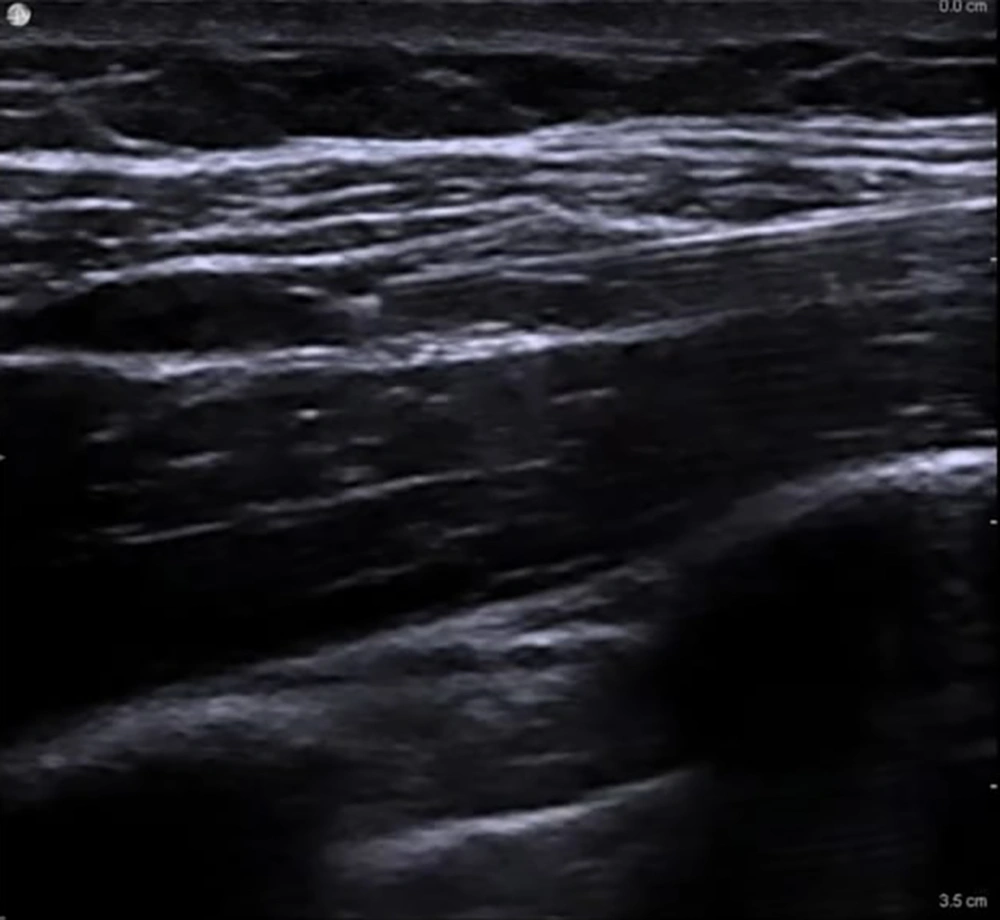

In all patients, the SCPB was performed before the assigned supplemental block (10). Patients were placed supine with the head turned approximately 30° away from the surgical side and a small towel positioned between the scapulae to optimize access. After aseptic preparation, a high-frequency linear US probe (6 - 12 MHz) covered with a sterile sheath was placed in the coronal-oblique plane just superior to the clavicle and lateral to the sternocleidomastoid muscle to visualize the subclavian artery medially, the brachial plexus divisions as a cluster of hypoechoic round structures lateral to the artery, and the first rib and pleura as hyperechoic lines deep to the artery. Using an in-plane lateral-to-medial approach, a 22-G, 80-mm insulated block needle was advanced under continuous US guidance toward the “corner pocket” bordered by the subclavian artery medially, the first rib inferiorly, and the brachial plexus laterally. After negative aspiration, 5 - 10 mL of 0.25% bupivacaine was injected into the corner pocket, and the needle was redirected to deposit additional 3 - 5 mL aliquots around the remaining plexus divisions to ensure circumferential spread, for a total of 20 mL. Proper injectate distribution was confirmed sonographically, and care was taken to avoid pleural puncture, vascular injection, or intraneural spread (Figure 1).